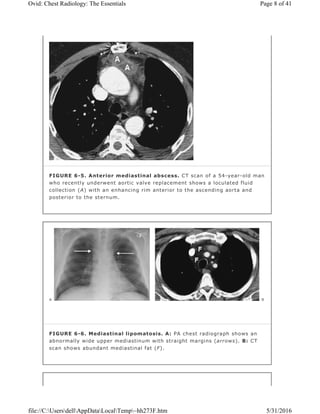

FIGURE 6-5. Anterior mediastinal abscess. CT scan of a 54-year-old man

posterior to the sternum.

FIGURE 6-6. Mediastinal lipomatosis. A: PA chest radiograph shows an

scan shows abundant mediastinal fat (F).